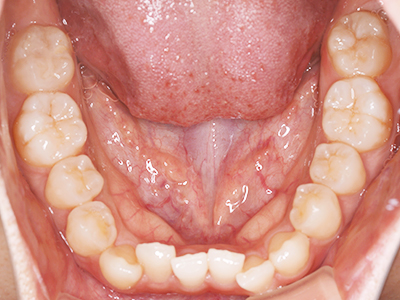

歯並びの相談に来られるお子様は、口呼吸をしているケースが多く、これが歯並びに大きな影響を与えています。

- 口呼吸をしている

↓ - 舌の位置が悪くなる

↓ - 頬の圧力が上の歯列にかかりやすくなる

↓ - 上あごが狭くなる

↓ - 下あごが狭くなる・下あごの位置が悪くなる

↓ - さまざまな不正咬合が生じる

ないき歯科クリニックでは、上あごの成長不足を補い、鼻呼吸を獲得しつつ歯列を整え、将来のお口をより健康な状態にすることをゴールに定める矯正治療をおこなっています。